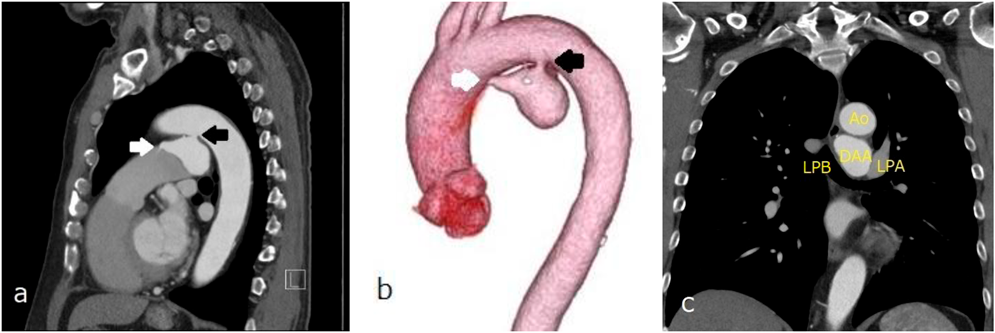

入院翌日に経皮的動脈管閉鎖術を施行した.局所麻酔後,右大腿静脈に6 Fr 11 cm sheath(Medikit Inc., Tokyo),右大腿動脈に5 Fr 11 cm sheath(Medikit Inc., Tokyo)を留置した.カテーテル検査の結果Qp/Qsは1.05,肺血管抵抗係数は0.57 Wood unit·m2.大動脈造影でDAAが造影され,瘤入口部径は5.4 mm,瘤最大径は28.9×37.2 mm,瘤流出部径は2.2 mmであった(Fig. 3a).5 Frジャドキンス型右冠動脈用(JR)カテーテル(Hanaco Medical, Saitama, Japan)を逆行性に進めて瘤入口部にかけて,そこから0.035̋Radifocus guidewire 260 cm(Terumo Inc., Tokyo)を瘤内へ進めて,1ループさせて主肺動脈まで進めた.続いて,順行性に進めて主肺動脈に留置した6 Fr wedge pressure catheter(Gadelius Medical, Kanagawa, Japan)から15 mm径の6 Fr Amplatz goose neck snare (Medtronic plc., Ireland)を進めて,Radifocus guidewire先端を把持して(Fig. 3b)右大腿静脈のsheath外まで引き出した.瘤内のループを伸ばして,大腿静脈–DAA–大腿動脈のwire loopを作成した(Fig. 3c).DAAの大動脈側入口部径が5.4 mmであったため,ADO 12 mm/10 mm(Abbott Structural Heart, Plymouth, MN, USA)を同部に留置した:右大腿静脈のsheathを抜去し,7 Fr Amplatzer™ TorqVue 180 (Abott, Pylmouth, MN, USA)を下行大動脈まで進めた.ADOのRetention skirtを展開して瘤入口部にかけて,デバイスボディを瘤内に展開した.留置後の大動脈造影では閉鎖栓突出による大動脈の狭窄はなく,遺残短絡はごく少量であった(Fig. 3d).特に合併症は認めず,治療翌日からアスピリン100 mgの内服を開始し,退院した.治療後の経過は良好で,術後1カ月の心臓超音波検査で遺残短絡は消失し,術後3カ月の胸部造影CT像で瘤内はほぼ血栓化していた(Fig. 4).

Pediatric Cardiology and Cardiac Surgery 41(2): 84-88 (2025)

Fig. 4 Contrast-enhanced chest computed tomography revealing that the DAA is almost thrombosed (black arrow)

DAA, ductus arteriosus aneurysm.